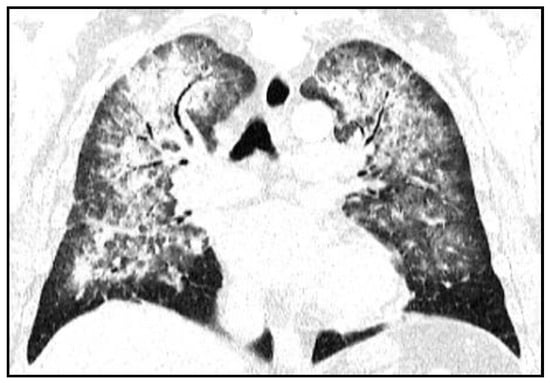

Initial investigations included chest computed tomography (CT), which evidenced in the lung, starting with the apex, a bilateral interstitial pattern with reticular appearance and in some places with ground-glass appearance, alternating with several areas of discrete condensation and positive air bronchogram in the upper lobes, anteriorly, more obvious to the left; in the middle lobes without condensation, radiological changes decreased in intensity towards the lung bases (Figure 1).

Figure 1.

Chest computer tomography scan showing signs of interstitial lung disease (admission).